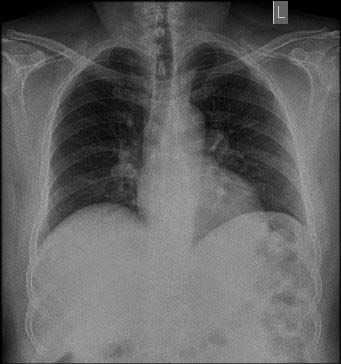

On examination he was febrile with temperature of 38.8c. His blood pressure was (80/40 mmHg), pulse was 120 and respiratory rate was 28/min. His abdomen was slightly distended with remarkable tenderness and rigidity over the right hypochondrium. Murphy's sign was positive. His ECG was normal and his blood gas analysis showed slight metabolic acidosis. His hemoglobin was (13 g/dl). Urea and electrolytes, liver function test and serum amylase were within normal values. His erect chest X Ray excluded free air under the diaphragm (Figure 1). After initial fluid resuscitation he had abdominal CT scan (Figure 2A & B) which showed a distended thickened wall gallbladder containing air within its wall and lumen with air-fluid level. There was also a curvilinear hyper density in relation to the gallbladder wall, with gallbladder wall calcification and pericholecystic fat stranding extending to the region of the hepatic flexure. There was no obvious evidence of gallstones seen and no evidence of intra-or extrahepatic biliary dilatation. The CT scan findings were consistent with non-calculus emphysematous cholecystitis. The patient did well and discharged on the 7 th post cholecystostomy day. The cholecystostomy tube was removed after 6 weeks and he remained symptoms free on follow up for more than a year.